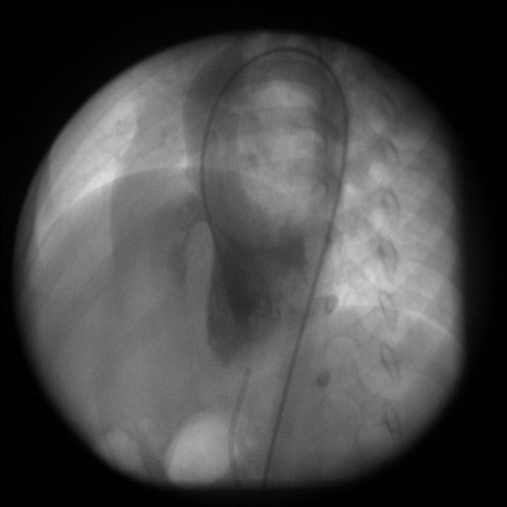

室间隔缺损:心血管造影表现

◇ 左室造影

长轴斜位显示膜周部VSD

◇ 心血管造影已不是诊断VSD的常规方法

◇ 在VSD封堵治疗时使用但效果不如超声监测